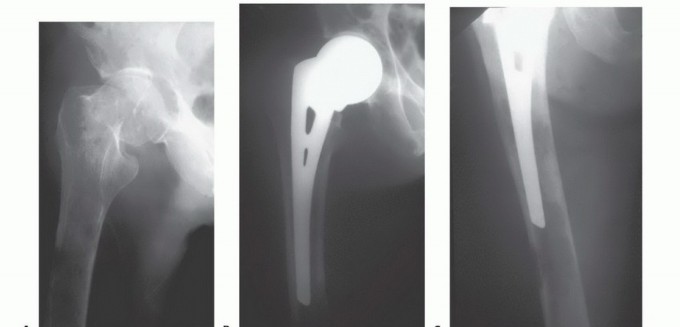

الشكل 2: أ. صورة أشعة سينية تظهر كسرًا مرضيًا في الورك لدى أنثى تبلغ من العمر 69 عامًا ولديها تاريخ معروف بسرطان الثدي. ب. أجريت عملية استبدال نصفي للورك خلال 24 ساعة من حدوث الكسر، ولكن صور الأشعة السينية بعد الجراحة أظهرت نقيلة إضافية أسفل طرف جذع الطرف الاصطناعي (ج) لم يتم اكتشافها بسبب سوء جودة صور الأشعة السينية قبل الجراحة ولأن صور الأشعة السينية للعظم بالكامل لم تُجرَ قبل الجراحة. د. بينما كانت لا تزال في المستشفى، عانت من كسر مرضي في تلك الآفة أثناء نقلها من سريرها إلى كرسي استلقاء.